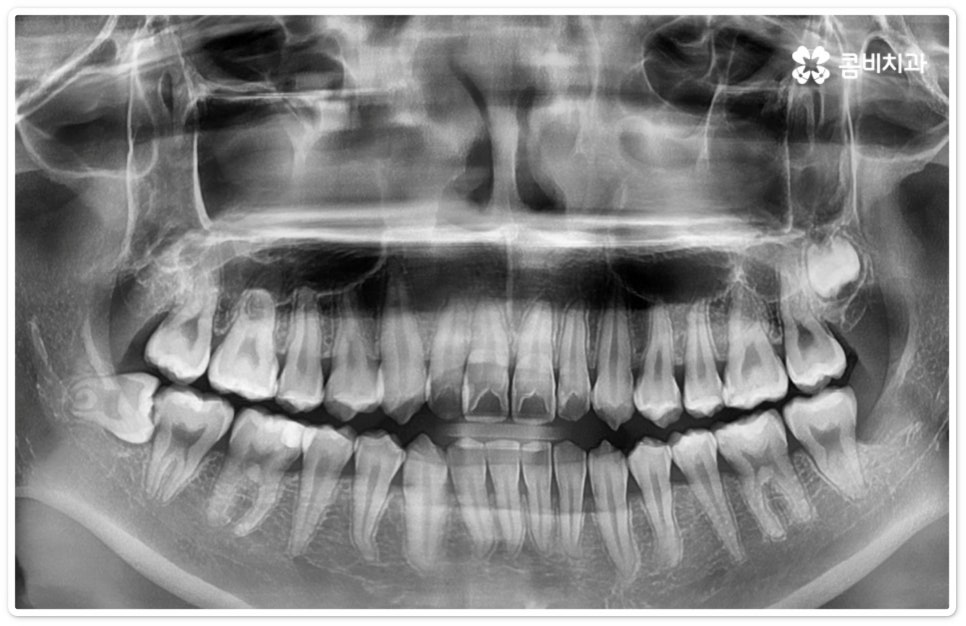

사랑니는 17세부터 25세 전후까지의 시기에 제일 늦게 나오는 치아로 만약 똑바로 맹출이 되었으며 관리를 하기에도 크게 어려움이 없는 경우라면 반드시 뽑아야 하는 것은 아니지만 자리가 비좁아 부분적으로만 나오거나 매복되어 누운 상태로 인접 치아에 악영향을 주는 경우라면 정확하게 검사를 한 후에 발치해 주는 것이 좋을 거예요. 가장 뒤쪽에서 자라나기 때문에 칫솔이 닿기 어려워 음식물이 잔류할 가능성이 높으므로 충치가 발생하거나 주변 잇몸에 염증이 생기기도 쉬운데요, 이런 경우 통증이나 냄새의 원인이 되고 인접 어금니까지 구강 질환이 번질 수 있기 때문에 주의하실 필요가 있어요.

우리나라 사람 중에 약 7% 정도는 사랑니가 아예 없다고 하지만 보통 25세가 지났는데 사랑니가 나오지 않았다면 매복 사랑니이거나 누워있는 사랑니인 경우가 많으므로 정밀 검진을 받아보실 필요가 있는데요. 이때 염증을 지속적으로 유발하거나 음식물이 끼면서 관리가 잘 안 되면서 발생하는 충치 등 좋지 않은 영향을 주고 있다면 발치 처치를 해 주는 게 좋은데, 20대에 누운사랑니발치 를 진행하는 것이 40대 이후에 하는 것보다 통증 및 출혈도 덜하고 회복도 빠를 수 있으니 이를 염두에 두시길 바라고 있어요.